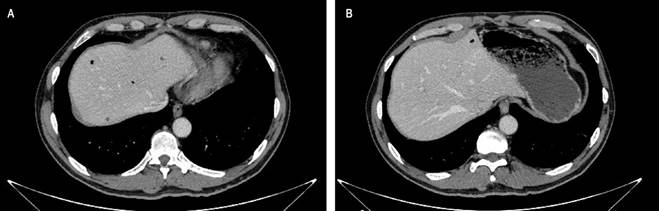

We present the case of a 62-year-old male patient who arrived at the emergency department with a three-day history of abdominal pain and distension, multiple episodes of diarrhea without gastrointestinal bleeding, nausea, vomiting, and fever. The patient attributed these symptoms to the consumption of spoiled meat. Upon admission, his vital signs were within normal limits. Physical examination revealed abdominal distension and tenderness on palpation, but there were no signs of peritoneal irritation. Analgesia was administered, and laboratory tests were performed, showing normal leukocyte levels (8,700), mild neutrophilia (85%), elevated C-reactive protein (4.9), normal renal function, and adequate electrolytes and acid-base status. Due to persistent pain, an abdominal and pelvic computed tomography (CT) scan was ordered. The axial CT scan revealed gas bubbles, predominantly in the region corresponding to the hepatic dome and the left hepatic lobe, suggestive of portal venous gas (Figure 1). There was also liquid and gaseous distension of the gastric chamber, with air dissecting the gastric wall, particularly at the fundus and along the greater curvature (Figure 2), findings consistent with gastric wall pneumatosis and non-specific thickening of the gastric walls at the antropyloric region.